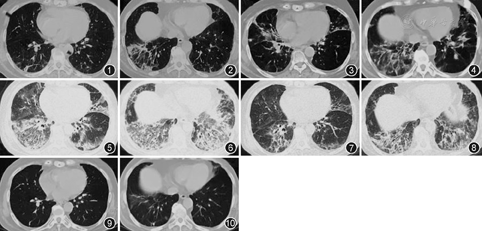

患者女,72岁,因"间断发热、咳嗽、咳痰2年,再发1周"于2016年1月24日入院。患者于2014年5月9日无明显诱因出现发热,最高体温37.9 ℃,伴咳嗽,咳少量白黏痰,无呼吸困难,当地医院给予头孢呋辛、莫西沙星治疗无效,体温升至38.3 ℃,并出现双腿乏力,上楼时需上肢协助支撑扶手。于当地医院住院查血常规大致正常,红细胞沉降率(ESR) 45 mm/1 h,肌酸激酶(CK)553 U/L,抗核抗体(ANA)谱:抗Jo-1抗体(+),ANA(-) ,胸部CT(2014年5月22日,图1,图2)可见双肺多发索条影,散在片状实变影,肌电图未见明显异常,考虑"间质性肺疾病合并感染",给予糖皮质激素(激素)治疗:甲泼尼龙40 mg,1次/12 h,静脉滴注,7 d后改为40 mg/d,静脉滴注,7 d后改为口服48 mg/d,联合多种抗生素治疗后临床症状逐渐缓解。出院后甲泼尼龙逐渐减量(每2周减4 mg)。2015年2月(口服甲泼尼龙2 mg/d)患者再次发热,最高体温37.9 ℃,伴咳嗽,咳白黏痰,活动后气短,复查胸部CT(2015年2月23日,图3,图4)可见双肺多发索条、斑片、磨玻璃影,再次住院,期间查肌炎抗体谱:抗Jo-1抗体:96 RU/ml(正常值<15 RU/ml);四肢肌肉核磁共振示"双下肢肌肉萎缩"(具体不详);支气管镜下右下叶后基底段肺活检示"肺泡间隔略增宽,可见不典型机化灶",右上臂肌活检病理示"符合炎性肌病表现"。考虑ASS,再次给予治疗(甲泼尼龙静脉滴注,40 mg,1次/12 h,3 d后改为40 mg, 1次/d)后症状逐渐减轻出院(口服甲泼尼龙40 mg/d)。出院后2周患者因顾虑激素的不良反应,自行调整为甲泼尼松20 mg,1次/d,并逐渐减量,至2015年8月口服甲泼尼龙2 mg/d并长期维持。2016年1月16日患者无明显诱因再次出现发热(体温最高38.3 ℃),伴咳嗽,咳少量白色黏痰,口服头孢克洛250 mg,2次/d,后体温升至39.9 ℃,并逐渐出现活动后气短,胸部CT(2016年1月23日,图5,图6)可见双肺病变明显加重,双肺(双下肺、左舌叶及右中叶明显)大片渗出影,部分为实变,为进一步诊治收入住院。追问病史发现患者2010年无明显诱因出现左侧肘部、右手拇指、示指桡侧皮肤粗糙。起病以来无雷诺现象或光过敏,无口眼干及关节肿痛。既往史:2014年应用激素期间曾有血糖升高,诊断为"类固醇性糖尿病",间断胰岛素对症应用。其余个人史、婚育史和家族史无异常。入院体检:血压132/72 mmHg(1 mmHg=0.133 kPa),脉搏72次/min,肢端氧饱和度91%,技工手、Gottron征阳性,双下肺可闻及爆裂音,心脏及腹部未发现阳性体征,上肢肌力正常,双下肢近端肌力Ⅴ-级,无压痛,双下肢不肿。

入院后完善系列辅助检查:血常规、尿常规、肝肾功能及电解质、血清免疫球蛋白及补体水平大致正常。动脉血气分析(不吸氧,静息):pH值为7.42、PaCO2为37.2 mmHg,PaO2为61.5 mmHg,HCO3-为24.4 mmol/L。血清CK为2 325 U/L,CK-MB为24.8 μg/L,血清肌钙蛋白I(cTnI)正常;ESR:34 mm/1 h,超敏C反应蛋白为22.67 mg/L;ANA18项:Ro 52强阳性(+++),Jo-1强阳性(+++),抗中性粒细胞胞质抗体、血清1,3-β-D-葡聚糖(G试验)及半乳甘露聚糖(GM试验)均阴性;痰送检多种病原学(包括细菌、真菌及MTB)均为阴性,心脏彩色多普勒超声提示左心室松弛功能减低,左心室射血分数69%,其余未见异常。结合病史及上述辅助检查结果,考虑抗Jo-1综合征、低氧血症,给予甲泼尼龙(40 mg,1次/12 h,静脉滴注14 d)、丙种球蛋白(10 g/d,5 d)、依诺肝素钠(6 000 U/d,皮内注射),第3天患者体温恢复正常,1周后咳嗽、活动后气短等临床症状逐渐改善,复查胸部CT(图7,8)。遂于2016年2月8日起调整方案为激素(口服泼尼松50 mg/d)联合免疫抑制剂(口服吗替麦考酚酯分散片0.5 g,2次/d)并出院门诊随诊。出院后2周起,泼尼松逐渐减量,至2016年6月5日为泼尼松15 mg/d,胸部CT可见肺内病变较前明显吸收(图9,10);建议维持目前剂量泼尼松3~5个月后逐渐减量,吗替麦考酚酯分散片维持剂量口服。随访至2017年1月(泼尼松减量至5 mg/d),患者病情平稳,日常活动无明显不适,复查胸部CT较前变化不大,继续门诊随访。

Marie等[11]、Stanciu等[12]和Zamora等[13]的报道显示,抗Jo-1-ASS的胸部CT表型以非特异性间质性肺炎(nonspecific interstitial pneumonia,NSIP)型为主,其次为机化性肺炎(organizing pneumonia,OP)型或NSIP合并OP型,少部分表现为(usual interstitial pneumonia,UIP)型。鉴于对于已临床诊断ASS的患者常规不推荐肺活检,尤其是外科肺活检。关于Jo-1-ASS的肺病理的文献并不多,Marie等[11]的报道中以NSIP型最多见,其次是OP、UIP型;Zamora等[13]的病例中则以OP最多见,其次为NSIP;少部分表现为UIP型和弥漫性肺损伤(diffuse alveolar damage, DAD)。但Yousem等[14]的报道中则提示,以UIP型最多见,其次是急性或机化性DAD型、纤维化性间质性肺炎基础上的急性加重,少部分表现为NSIP型,但其研究对象中除了常规的抗Jo-1-ASS患者外,还有一部分是尸检标本、抗Jo-1-ASS受者接受肺移植术后的移除肺。本例患者的多次急性加重阶段的胸部CT表现以NSIP并OP型为主。鉴于患者在本次入院后结合临床表现、血清学表现确诊为抗Jo-1综合征而未安排肺活检;不过她在第二次急性加重阶段的经支气管镜肺活检提示肺内有"不典型机化灶"。